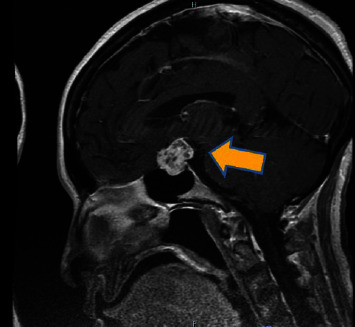

In this report, we present the case of a 71-year-old African-American woman experiencing 2 months of intermittent headaches and episodes of blurred vision. Despite a comprehensive medical history that revealed chronic conditions and previous unrelated surgeries, the initial evaluation appeared to be unremarkable. Following the discovery of a mass on an imaging and a subsequent biopsy, the diagnosis of craniopharyngioma (WHO grade I) was confirmed. However, a brain mass was identified after additional ophthalmologic examination and MRI. This case explores the significance of recognizing atypical presentations of a brain injury that required a specific approach for diagnosis, surgical intervention and treatment, and postoperative care. This case contributes to the constantly evolving understanding of atypical manifestations of tumor characteristics and their complexities, along with the need to develop appropriate patient management strategies and provide optimal outcomes.